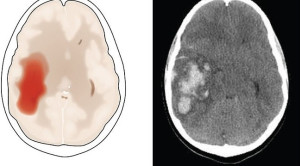

• Diagnosis Peningkatan Tekanan Intrakranial: Akurasi Tanda Klinis dan Pencitraan

Diagnosis Peningkatan Tekanan Intrakranial: Akurasi Tanda Klinis dan Pencitraan

Diagnosis peningkatan tekanan intrakranial menjadi tantangan tersendiri bagi klinisi karena sulit dilakukan hanya berdasarkan tanda klinis dan pencitraan. Baku emas pemeriksaan tekanan...(Baca Selengkapnya)